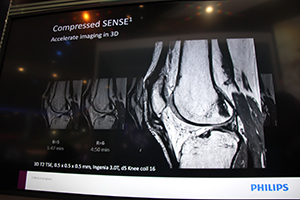

More accessibleは,1回の検査で確実に診断するというコンセプト“First time right”や,速く,直感的な操作性で,快適に検査を受けられる,より身近なMRIをめざすというもの。現在の到達点として紹介されたのが,映像と音楽で快適な検査環境を演出する“In-Bore Experience”で,息止めや検査の残り時間を映像にわかりやすく表示する最新バージョンを,3T MRI装置「Ingenia 3.0T」のモックアップとともに展示した。In-Bore Experienceは日本国内ですでに10台以上の装置にインストールされており,ユーザーからの評価は高いという。そして,リリース直後,あるいは間近のMore accessibleのアプリケーションとして,撮影時間を大幅に短縮する“MultiBand SENSE”と“Compressed SENSE”(W.I.P.)を紹介した。このうちCompressed SENSEは,コンプレストセンシング(圧縮センシング)とSENSE法を融合させ,画質を担保しながら,スキャン時間の短縮が可能になる。3Dスキャンにも対応し,わずかな時間で軟部組織や微小病変の信号も損なうことなく画像を取得できる。

3Dも含め短時間スキャンを可能にする |